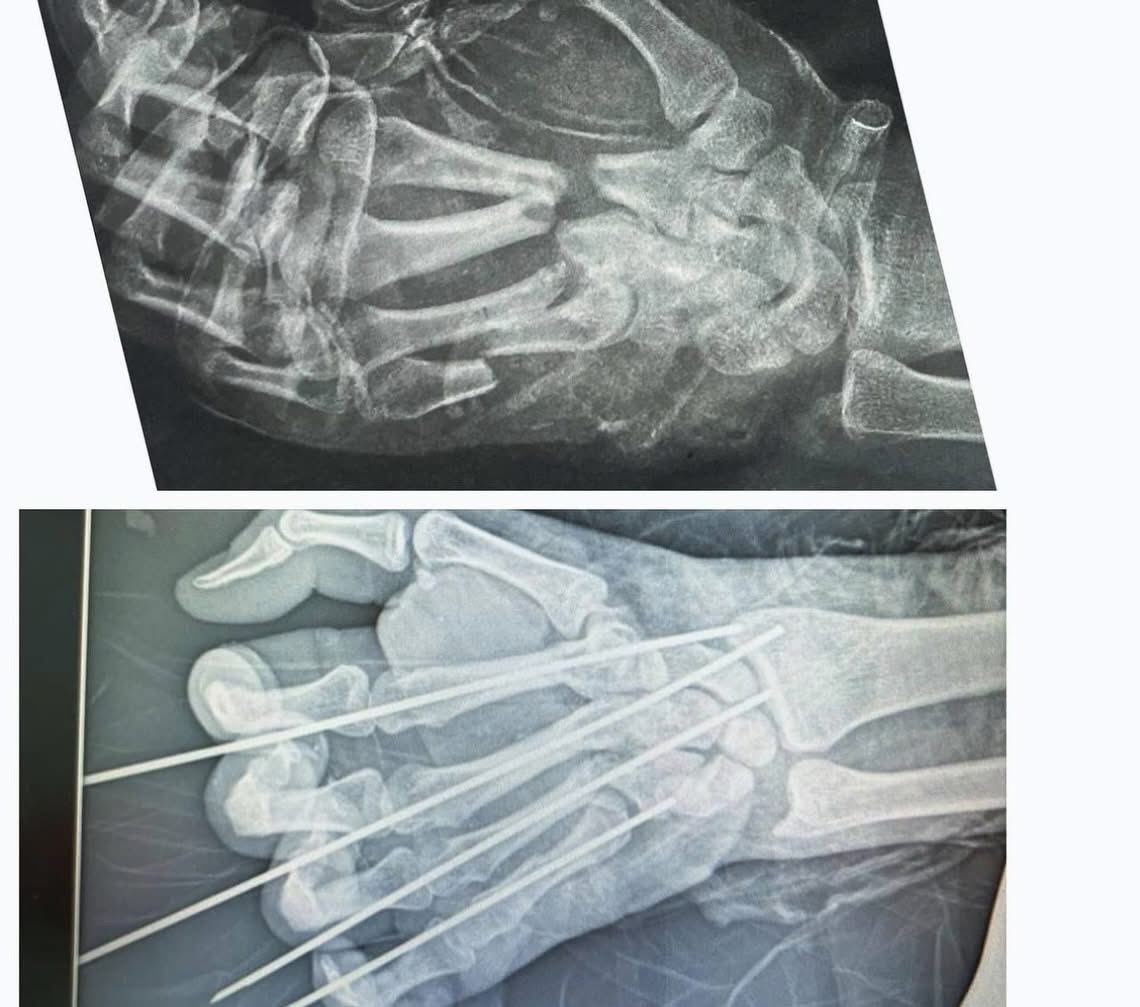

Напередодні вихідних до приймального відділення КНП «Міська клінічна лікарня» у важкому стані поступив 23-річний пацієнт із побутовою травмою правої кисті.

У результаті необережності він отримав неповну травматичну ампутацію тильної поверхні кисті з переломами п’ясткових фаланг 2-5 пальців та пошкодженням глибоких і поверхневих сухожилків розгиначів цих пальців.

Командою хірургів було проведено складну реконструктивну операцію:

• первинну хіруртичну обробку рани (ПХОР),

• остеосинтез спицями другого-п’ятого пальців,

• тенорафію сухожилків розгиначів кисті,

• встановлення дренажів.